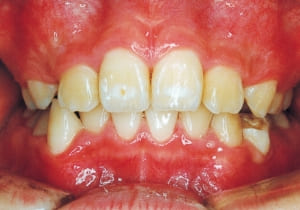

2 After Phase 2 Treatment 6-6-’94

The first phase of treatment involved extracting the left and right maxillary deciduous canines. The space created was used to forcibly retract the four anterior teeth, thereby aiming to improve lip closure function (6–9, 11). Morphological changes suggest that lip function differed before and after treatment (6, 9). Subsequently, the first premolars erupted, but extraction is planned to secure space for canine eruption (10). A Class II molar relationship remains, but the significant overjet has improved (11).